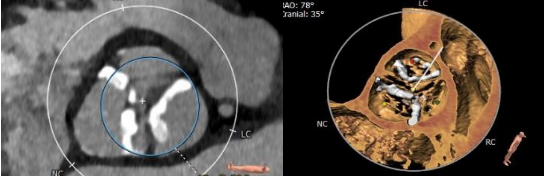

患者71岁老年女性,体重42kg,身高156cm,因突发活动后心累气紧合并心绞痛急诊入院,超声提示主动脉瓣膜重度狭窄,左心功能减低EF 46%,主动脉瓣峰值流速5.2m/s, 平均跨瓣压差68mmHg(图1),冠脉造影提示冠脉未见明显狭窄,患者合并COPD,TIA等并发症,STS评分>6分,经外科团队讨论提示传统外科高风险,经过多学科讨论拟行TAVR手术。术前CTA评价提示三叶式主动脉瓣(图2),Area 479.2mm²,Perimeter 77.9mm,Area折算瓣环直径24.7mm,左侧冠脉开口高度16.1mm,右侧冠脉开口高度16.5mm,瓣膜重度钙化,主要分布于瓣叶,LVOT无特殊,主动脉窦平均内径31mm,患者外周血管尚可无明显钙化扭曲,最细5.9mm(图3)。

图2. 主动脉瓣三叶式,瓣膜增厚存在重度钙化,钙化分布较为均匀